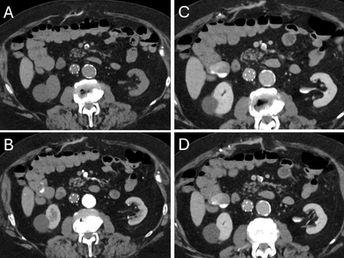

Active Bleeding in the Ascending Colon

An 83-year-old male with rectal bleeding. What is the diagnosis? • Xray of the Week Figure 1. CTA abdomen/pelvis. What is the diagnosis? Figure 2. CT angiogram: A. Non-contrast images are normal (yellow arrow) . B. Arterial phase image: Hyperdense extravasation of contrast within the lumen of the ascending colon (blue arrow), indicating active bleeding. C and D. Note the dependent layering of contrast on portal venous phase images, confirming active extravasation. Diagnosis A